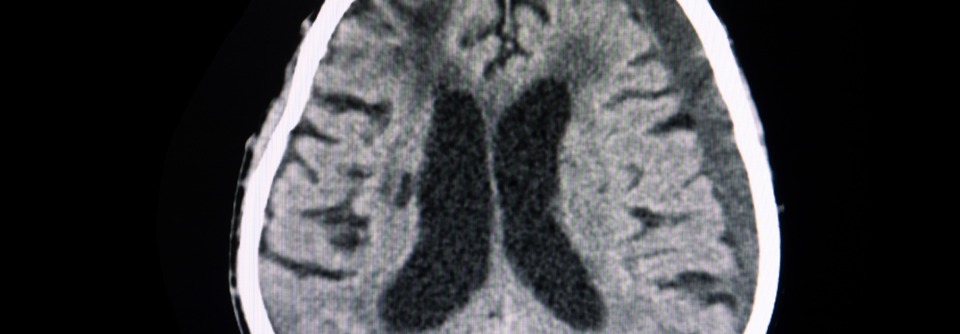

Jeder zweite Patient mit chronischer Cephalgie verdankt diese einer übermäßigen Anwendung von Analgetika oder Migränemitteln. Mindestens zwei Drittel von ihnen wären kopfschmerzfrei, wenn sie auf ihre oft eigenmächtige Therapie verzichten würden.

Voraussetzung für die Diagnose eines medikamentös bedingten Kopfschmerzes ist das Auftreten an > 15 Tagen im Monat bei vorbestehender Cephalgie. Außerdem muss der regelmäßige Übergebrauch von mindestens einem Akuttherapeutikum länger als ein Vierteljahr bestehen. Nicht-opioide Monoanalgetika werden an mindestens 15 Tagen im Monat eingenommen, koffein- oder codeinhaltige Kombinationen, Opioide, Triptane und Ergotamine mindestens an zehn Tagen.